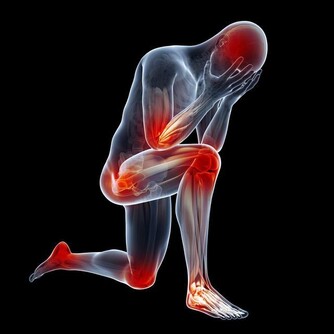

「養樹護根,養人護腳」。雙腳是運行氣血、聯絡臟腑、溝通內外、貫穿上下經絡的重要起始部位。

當腳部出現一些癥狀或者變化時,往往能反映出身體的某些健康問題。

信號一:抽筋

△健康徵兆:

1、外界環境的寒冷刺激,如冬季夜裡室溫較低,

睡眠時蓋的被子過薄或腿腳露到被外,都有可能引起腳部痙攣。

2、疲勞、睡眠、休息不足或休息過多,會導致局部酸性代謝產物堆積,引發痙攣。

3、骨質疏鬆,血鈣水平過低,肌肉應激性增加,也可導致痙攣的發生。

△解決對策:

①預防冬季腿腳抽筋,首先要做好保暖,睡覺時盡量不要長時間仰卧或俯卧,

可避免小腿肌肉長時間放鬆導致的肌肉攣縮;

②用熱毛巾、熱水袋敷於腿肚處,能有效促進肌肉的血液循環,緩解痙攣;

③骨質疏鬆人群,可增加鈣、鉀和鎂的攝入,睡覺之前喝杯熱牛奶,是很好的補鈣習慣。

信號二:腳麻

1、中風:對於患有高血壓、高血脂、動脈硬化等心腦血管疾病的人來說,腳麻可能是中風的先兆;

這類患者還多會伴有一過性的黑蒙、失語、聽力改變、說話模糊等。

2、腰椎間盤突出:由於坐骨神經受到壓迫,因此容易出現腳麻,此疾病大多還會伴有腰疼、腿疼等。

3、糖尿病併發症:糖尿病患者血糖升高時,會引起神經纖維一系列的代謝紊亂,

從而導致周圍神經病變,產生四肢末端麻木等情況。

①因血液流通不暢所造成的偶爾性腳麻,可以通過跺腳、捶打腳部及腿肚等方式進行緩解;

②如有不明原因的經常性腳麻,或因其他疾病所引起的腳麻,應及時到醫院就醫,對症治療。

信號三:腳腫

信號四:腳掌疼